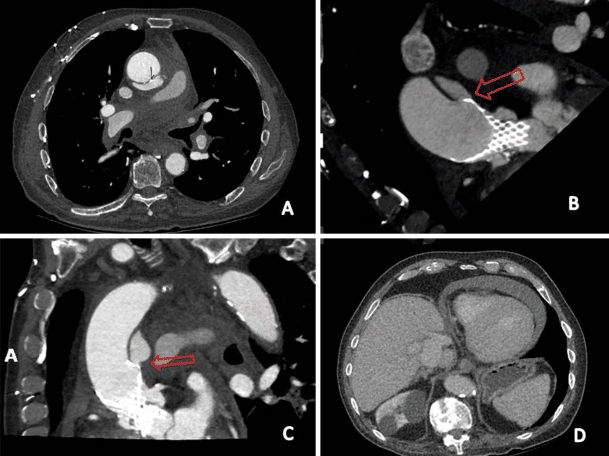

Nineteen days after TAVI, the patient was urgently readmitted to our hospital because of acute chest pain, accompanied by severe shortness of breath and hypotension. At our emergency department we saw a critically ill patient with clinical signs of cardiac tamponade. Systolic blood pressure decreased from 100 to 60 mmHg and was restored with intravenous fluid suppletion. Urgent echocardiography showed 2 cm of pericardial effusion with right ventricular diastolic collapse and marked under-filling of the left ventricle. The diagnosis was ‘acute cardiac tamponade’, probably as a late complication of TAVI. Urgent CT showed periaortic haematoma and contrast extravasation (Fig. 1a) at the level of the distal site of the prosthesis. The distal stent strut was located outside the ascending aorta towards the pulmonary artery continuation (Fig. 1b and c). CT confirmed the echocardiographic view of pericardial effusion (Fig. 1d).

Fig. 1

a periaortic haematoma and contrast extravasation at the level of the distal site of the prosthesis. b and c The distal stent strut was located outside the ascending aorta towards the pulmonary artery continuation. d CT confirmed the echocardiographic view of pericardial effusion